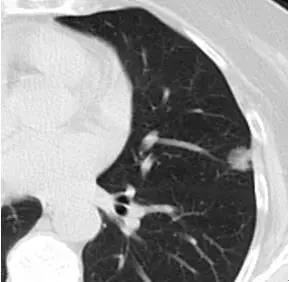

2. 胸膜凹陷

3. 支气管充气征

4. 荷包蛋型